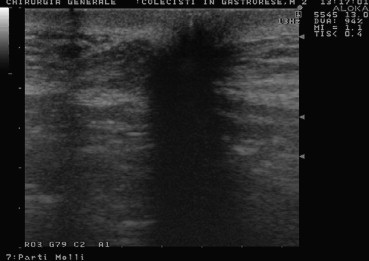

Fig. 2.

US shows regular slide of peritoneum in a patient with previous gastrectomy.

Fig. 3.

Same case is shown using a small parts probe at 13 MHz scanning frequency.